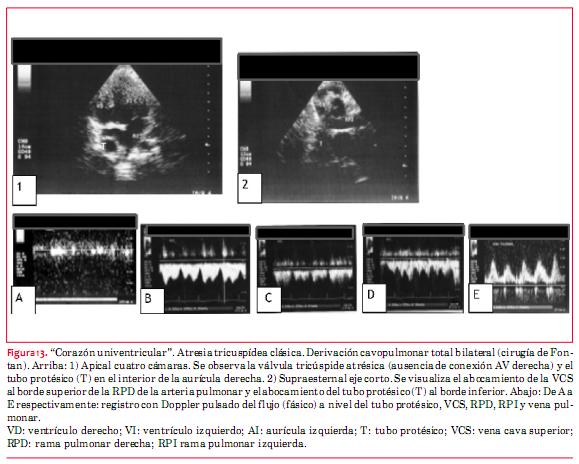

La cirugía de Fontan deriva el retorno venoso sistémico directamente hacia la rama derecha de la arteria pulmonar. Esta derivación se realiza quirúrgicamente en dos etapas. La primera abocando directamente la VCS al borde superior de la rama pulmonar derecha. La segunda derivando por intermedio de un tubo protésico el flujo procedente de la VCI al borde inferior de la misma arteria pulmonar.

La energía para este modelo circulatorio procede del único ventrículo disponible para ello, que funciona como ventrículo sistémico y por “vis a tergo” mantiene la circulación arterial pulmonar.

Como consecuencia, la circulación pulmonar deja de ser pulsátil y se transforma en una circulación fásica de tipo venoso. Esta es la característica fundamental que debe evaluarse mediante la técnica Doppler, para asegurar que el sistema está funcionando de modo adecuado. Utilizando Doppler pulsado deben obtenerse registros del tubo protésico, de la VCS, VCI, ambas ramas de la arteria pulmonar y de las venas pulmonares (figura 13). La presencia de flujo continuo implica obstrucción. Los aspectos morfológicos son de menor importancia que lo señalado precedentemente. Sin embargo debe efectuarse una evaluación minuciosa en búsqueda de trombos en los distintos sectores de la circulación de Fontan (venas cavas, tubos protésicos y ramas de la arteria pulmonar). Finalmente resulta de capital importancia evaluar la función sistólica y diastólica del único ventrículo viable, de cuya funcionalidad depende todo el sistema. En este aspecto resulta de importancia, además, valorar los aspectos funcionales (estenosis o insuficiencia) de la o las válvulas auriculoventriculares, lesiones obstructivas (valvular, subvalvular o supravalvular) o incompetencia que pudieran asentar a nivel aórtico. Cuando la aorta emerge del ventrículo hipoplásico (no viable), adquiere relevancia la evaluación en búsqueda de obstrucción, de la CIV o foramen bulbo-ventricular, que permite la comunicación entre ambos ventrículos.